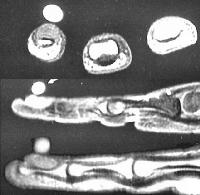

MRI demonstrated a dorsal subungual contrast enhancing mass.